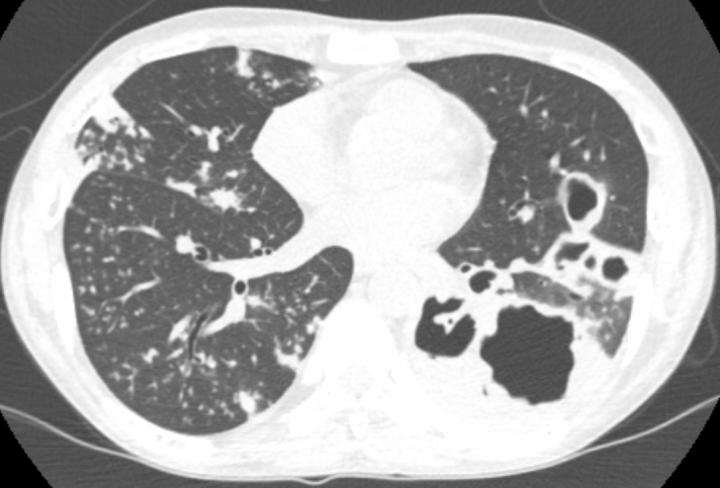

image: Lung damage caused by TB infection

Surprisingly, immune activation with checkpoint inhibitors can sometimes lead to rapidly progressive tuberculosis, an infection that used to kill one in three people in the UK. Researchers in the Faculty of Medicine at the University of Southampton described one of the earliest cases of immunotherapy-associated tuberculosis in December 2018 in the American Journal of Respiratory and Critical Care Medicine, and reports of similar cases have progressively accumulated. However, the true incidence is unknown as progression of cancer and the development of tuberculosis can be similar.